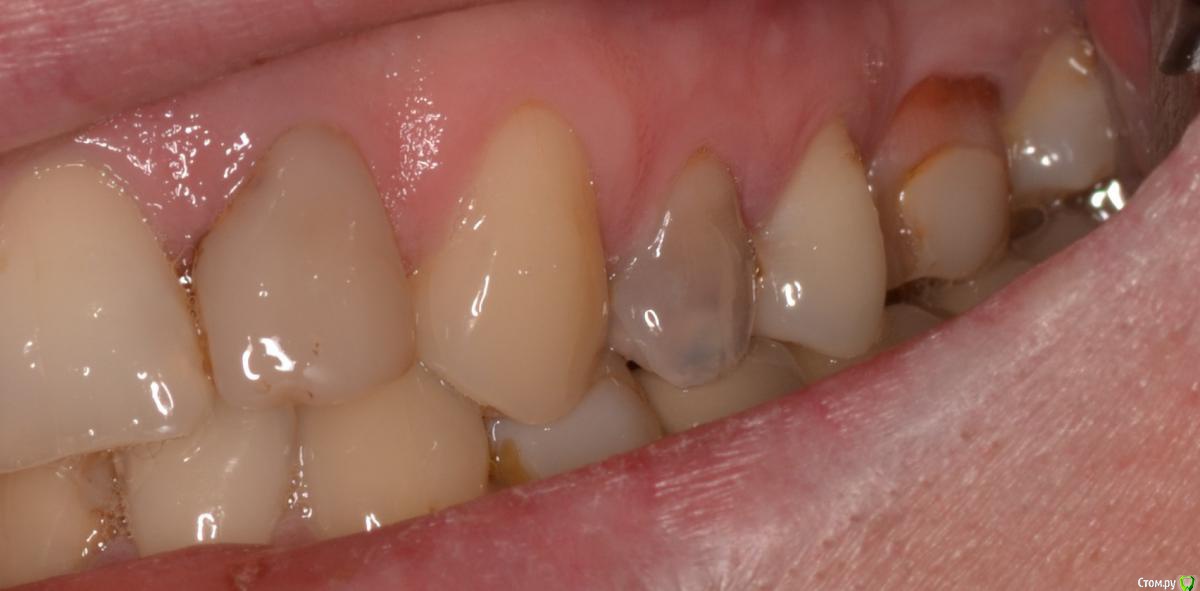

Военный Врач Опубликовано 5 апреля, 2016 Поделиться Опубликовано 5 апреля, 2016 Удалили и прикрутили. между имплантацией и снятием швов 9 суток. лунку закрывал тканями с бугра 18 Ссылка на комментарий